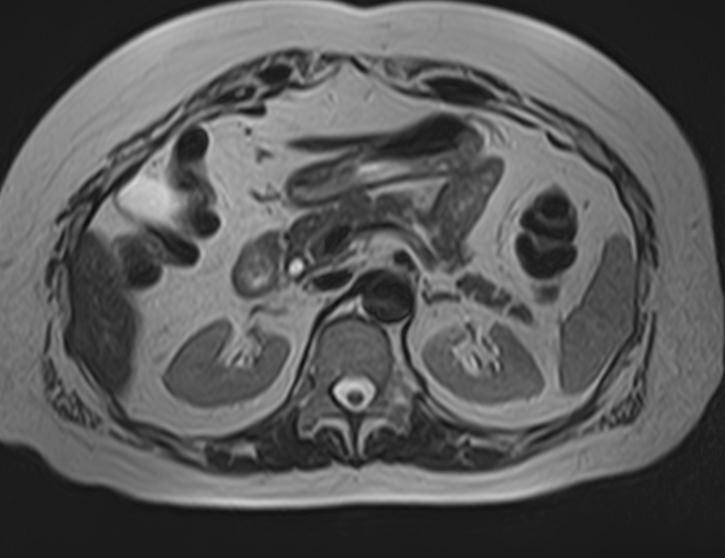

МРТ почек проводится для оценки состояния всех структур этого важнейшего органа выделительной системы, включая паренхиму, чашечки, лоханки почек и сосудистую систему. В клинике «Доступная медицина» исследование выполняется на томографе экспертного уровня TOSHIBA VANTAGE TITAN 1,5 Тесла, который обеспечивает изображения высокой четкости и контрастности, что позволяет проводить точную и достоверную диагностику заболеваний почек.

МРТ используется для диагностики злокачественных и доброкачественных опухолей почек. При этом большую ценность представляет МРТ почек с введением контрастного вещества. Процедура дает возможность не только выявить новообразования, но и установить степень развития патологического процесса, определить распространение метастазов на близлежащие органы. Только МРТ позволяет обнаружить псевдокапсулу новообразования. Такая информация крайне необходима, если речь идет об оперативном лечении рака почки с возможным сохранением органа. Также методика с высокой точностью определяет кистозные образования, распространение метастазов.

МРТ почек показывает:

- размеры мозгового и коркового слоев;

- расположение анатомических структур органа;

- функциональность;

- возможное вовлечение в патологический процесс питающих сосудов.

Исследование используется при лечении различных воспалительных и дегенеративных процессов почек с целью анализа эффективности проведенной терапии. МРТ почек назначается пациентам при наличии противопоказаний к осуществлению рентгенограммы, урографии, в случае неэффективности КТ, ультразвукового сканирования. Дополнительно во время обследования диагност может выявить заболевания мочевыводящих путей, в частности, мочеточников. Показано проведение магнитно-резонансной томографии при эндокринных патологиях (при расстройстве функций надпочечников), злокачественном течении гипертонической болезни. С помощью МРТ почек удается установить травматические повреждения, подтвердить абсцесс органа, мочекаменную болезнь, врожденные аномалии строения.